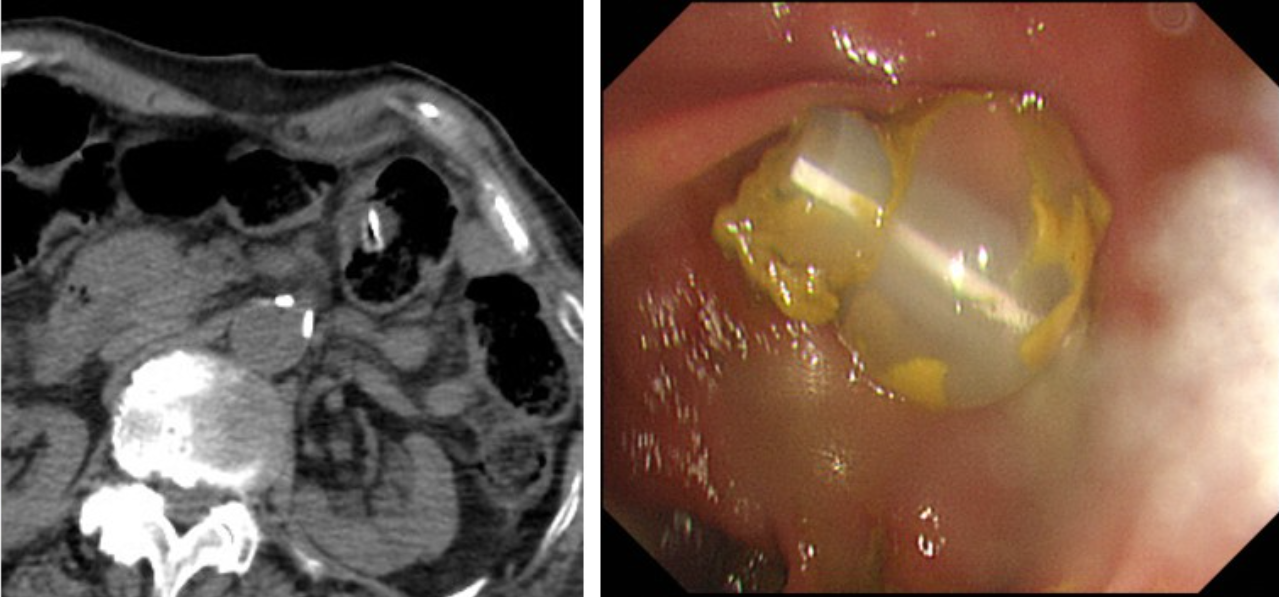

PEG tube를 처음 삽입할때(PEG tube 처음 만들때)는 공기를 최대한 주입해서 하므로 위가 복벽에 가까이 위치하지만 PEG tube를 교체할때는 위의 음식물이 없는상태이므로 위는 주먹만하게 작아진 상태입니다.

따라서 그때는 복벽과 떨어지는 경우가 매우 많습니다.

교체시 심각한 합병증(위치이탈,공기배증) 및 이로인한 감염, 복막염, 패혈증 등으로 사망위험이 있습니다.

malposition, replacement into colon or liver